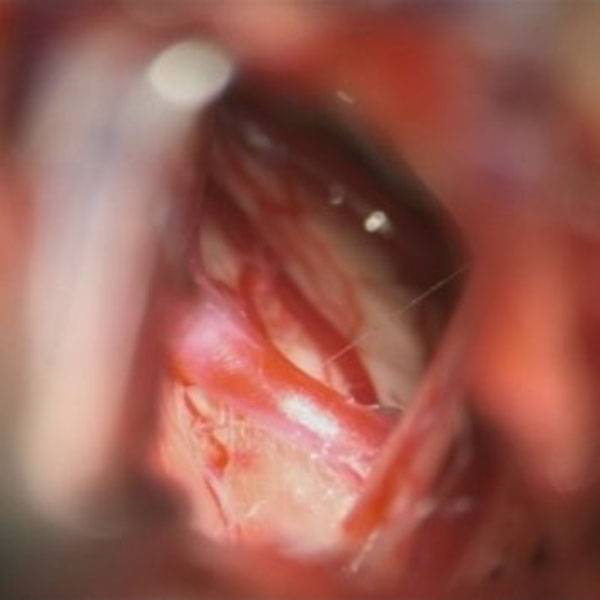

手術中

処置前

処置後